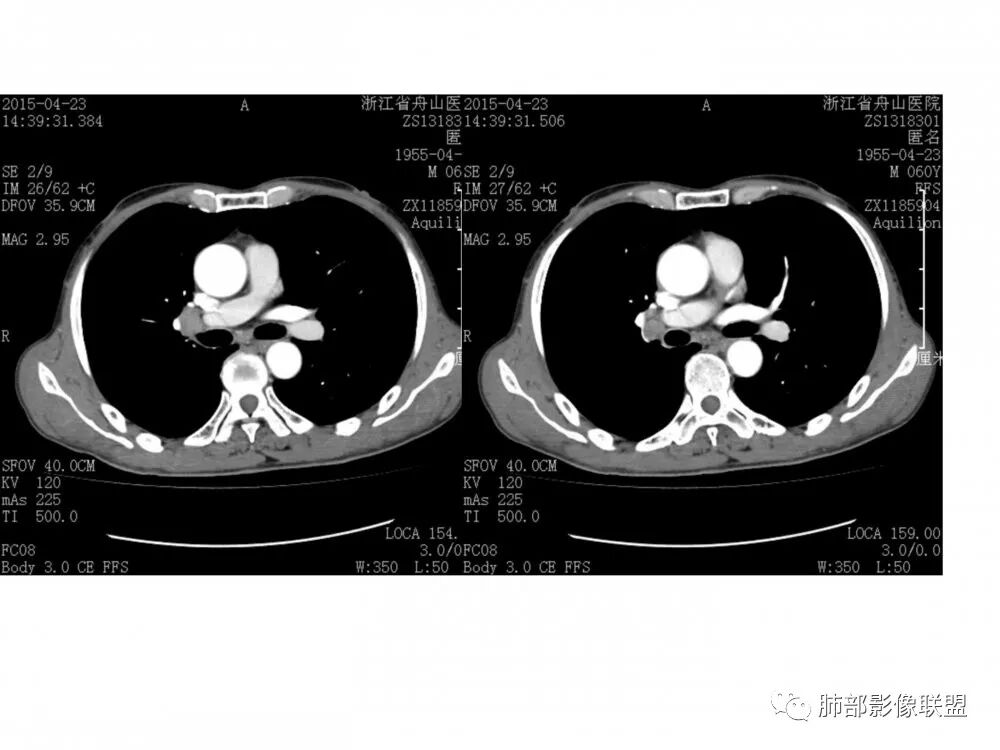

右中间、右下叶背段支气管管腔内见突向管内的管状软组织影,相邻支气管壁有侵犯,增强有强化,纵隔2R 、4R、10R组淋巴结肿大,增强有强化,未见ct值,常规考虑恶性肿瘤,小细胞癌并同侧纵隔淋巴结转移,鳞癌、类癌街排,建议支气管镜检查。

右肺下叶支气管腔内肿块,沿着支气管生长,支气管壁破坏,中度强化,纵膈及肺门淋巴结肿大,老年男性,首先考虑小细胞肺癌,其次腺样囊腺癌。类癌女性多见,明显强化,淋巴结肿大少见。鳞癌常有远端阻塞炎症及肺不张,淋巴结肿大少见。

男,60岁,右侧肺门肿块影,右肺下叶支气管壁增厚,管腔狭窄,截断,增强扫描,病灶明显强化,密度不均,纵隔内见多发肿大淋巴结,考虑腺癌可能,鉴别鳞癌,小细胞癌。

右肺下叶支气管开口新生物,轴位管腔及纵向基底干大部分受累狭窄,支气管管壁破坏并突破形成腔外肿块,血管累及变细,肉眼观轻度强化,右肺门、纵膈淋巴结肿大,恶性没问题,阻塞性炎症不明显,类癌强化明显不支持,老年男性,首先考虑小细胞癌,鉴别不典型鳞癌和腺癌。

病理结果:鳞癌

1.鳞癌:多见于男性,抽烟史。可朝腔外生长,多为类圆形,偏心狭窄或环形增厚,常合并坏死,强化不等。生长在大支气管的鳞癌阻塞严重,周围会有明显阻塞性肺炎和肺不张。淋巴结转移相对较迟。